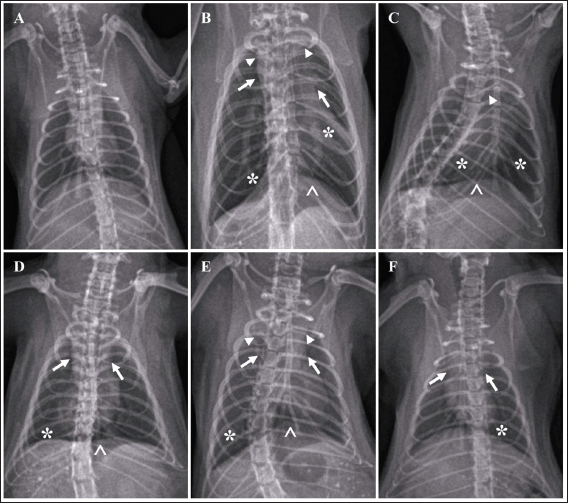

A significant difference was found between group G2 (untreated) and group G1 in terms of lung radiograph scores (p < 0.05). Groups G3 and G5 exhibited lung radiographs similar to those of group G2 (p > 0.05). Moreover, groups G4 and G6 showed lung repair after treatment compared to group G2 (p < 0.05). In several parameters, groups G4 and G6 did not exhibit differences compared to G1, especially in lung retraction scores and pleural effusion (p > 0.05). Group G6 also displayed better outcomes in lung radiographs than G4, particularly regarding the alveolar pattern and widened mediastinum (p < 0.05). Furthermore, group G6 did not differ from G1 in terms of mediastinal lesions (p > 0.05) (Table 4). A qualitative assessment of the lung radiograph is presented in Figure 3.

Fig. 3. Radiograph of rats’ lung after treatment. Typical lung image of the healthy rats from group G1 (A); the infected rat without treatment from group G2 showed a diffuse lesion on the lung marked by the widened of the mediastinum (arrow) with the retraction of the caudal portion of the lung (arrowhead), alveolar pattern (*) with the pleural effusion (^) (B); the group G3 showed the similar radiographic pattern with group G2 (C); group G4 indicated the focal alveolar pattern (*) with minimal pleural effusion (^) and mediastinum is widened (arrow) (D); moderate lesion of the lung from group G5 marked by widened of mediastinum (arrow), lung retraction (arrowhead), lobular alveolar lesion (*) with pleural effusion (^) (E); and minimal alveolar lesion (*) and the retraction of lung and widened of mediastinum still observed (arrow) from group G6 (F).